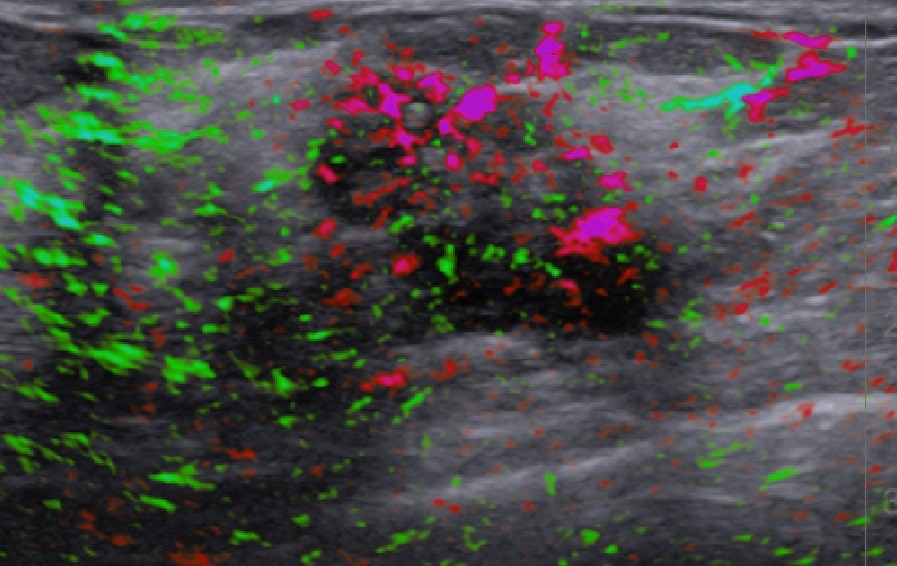

See deoxygenated blood in a sample Imagio® scan

In general, malignant masses are more vascular and deplete oxygen from the blood at a higher rate than do benign masses. The two wavelengths of laser light used in the Imagio® system facilitate imaging by showing the relative differences between oxygenated and deoxygenated blood.

"Optoacoustic imaging quantifies additional functional information on tumor biology,… “paralleling” the dynamic data obtained with breast MRI, contrast-enhanced mammography, and molecular breast imaging, though without the cost of magnet time, ionizing radiation, or risk of allergic reactions from gadolinium-based or iodinated contrast material."